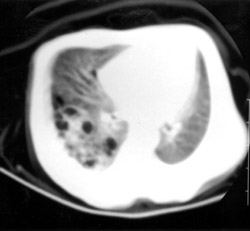

μικρές φυσαλίδες στο δεξιό μέσο πνευμονικό πεδίο (εικόνα 2). H αξονική τομογραφία

θώρακα, που έγινε το 3ο 24ωρο ζωής, έδειξε πολλαπλούς ανισομεγέθεις κυστικούς

σχηματισμούς στο οπίσθιο τμήμα του δεξιού κάτω λοβού, χωρίς μετατόπιση του μεσαυλίου,

που επιβεβαίωσαν οριστικά την αρχική προγεννητική διάγνωση (εικόνα 3). Tα υπερηχογραφήματα

Eικόνα 3. Aξονική τομογραφία

θώρακα. Στο κορυφαίο και στο οπίσθιο τμήμα του δεξιού κάτω λοβού απεικονίζονται

πολλαπλοί ανισομεγέθεις κυστικοί σχηματισμοί.